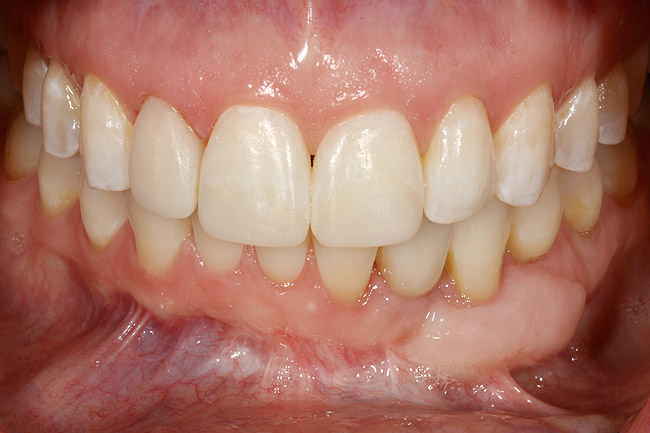

Figure 2  A preoperative retracted anterior view of the failing implant in the site of tooth No. 22.

Figure 2